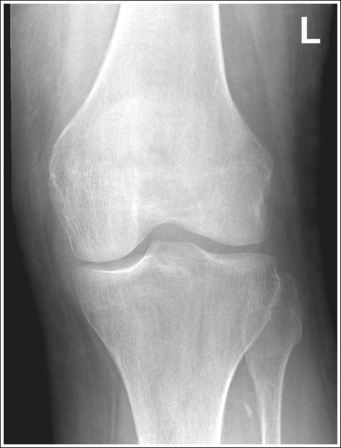

• Analysis of joint space narrowing. On an AP knee projection with adequate positioning, joint space narrowing is evaluated by measuring the medial and lateral aspects of the knee joint, which are also referred to as compartments. The measurement of each of these compartments is obtained by determining the distance between the most distal femoral condylar surface and the posterior condylar margin of the tibia on each side. Comparison of these measurements with each other, with measurements from previous images, or with measurements of the other knee determines joint space narrowing or a valgus or varus deformity. In a valgus deformity the lateral compartment is narrower than the medial compartment; in a varus deformity the medial compartment is narrower (see Images 56 and 57). Precise measurements of the compartments are necessary to ensure early detection of joint space narrowing and are best obtained when the knee joint space is completely open. If an inaccurate central ray angulation was used for an AP knee projection, the knee joint is narrowed or obscured, the intercondylar eminence and tubercles are foreshortened, and the tibial plateau is demonstrated.

The medial knee joint space is closed, and the fibular head is elongated and demonstrated less than 0.5 inch (1.25 cm) distal to the tibial plateau. Excessive caudal angulation is indicated.

If an open medial knee joint space is desired, the central ray should be adjusted cephalically.